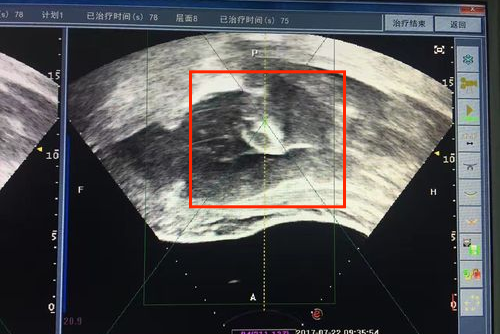

对于子宫肌瘤需要结合肌瘤大小、部位、有无症状、年龄及生育要求等进行综合考虑。若肌瘤小且无症状,可随访观察。如为有症状的小肌瘤或已近绝经者,可考虑药物治疗。若上述治疗无效,或肌瘤大于三个月妊娠子宫,生长迅速及有恶变可能者,可考虑进行手术切除。